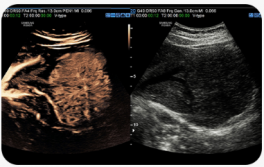

Zobrazení průtoku krve v cévách ve 3D zobrazení |

LumiFlow™ je funkce, která vizualizuje průtok krve v trojrozměrné podobě a pomáhá pochopit strukturu krevního toku a strukturu malých cév.